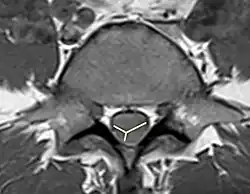

To identify the hematoma in the spinal cord, MRI with and without gadolinium enhancement is the preferred choice.[9] CT is also used to identify the hemorrhage and provide evidence for pathological analysis. Complete spinal MRI with MR angiography is used when patients with subarachnoid hemorrhage without the intracranial etiology.[20] As the evaluation of the need for intradural interrogation is important, it is necessary to differentiate between subdural and epidural hematomas. Based on the location of the hematoma, use both axial and sagittal images of MRI to identify the boundary between hematoma and fat.[7] An inverted Mercedes-Benz sign shows the spinal subdural hematoma on the axial image.[21]